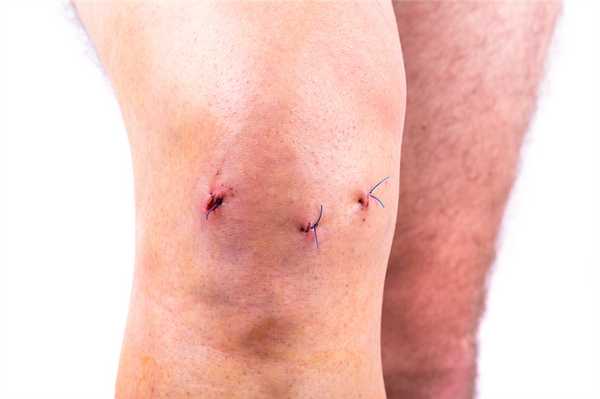

Когда еще не сняты швы.

- обработку раны, наложение стерильной повязки для профилактики ее инфицирования;

- Нельзя мочить операционный шов, следить за тем, чтобы он оставался сухим и чистым. Вопрос о принятии водных процедур следует согласовать со специалистом.

- На асептическую обработку и перевязки пациенту нужно являться к врачу каждые два дня на протяжении 7-12 суток. Возможно, если в суставе будет выявлено скопление выпота, в момент контрольных посещений сделают его эвакуацию при помощи пункции. Швы снимаются не ранее чем по истечении недели.